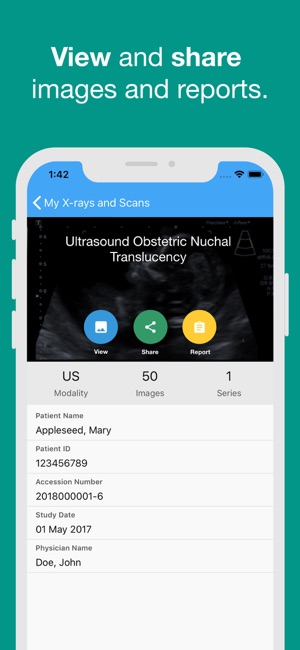

Having immediate access to X-rays and scans may give doctors and other health professionals, such as physiotherapists and chiropractors, a more complete picture of your relevant medical history.

You might want to look at your images again, when you are not at your doctor’s surgery. Or, you may wish to share a special scan with family or friends.

X-rays and scans are an important part of your medical history in the same way as previous medications and blood tests are important. Having immediate access to X-rays and scans may give doctors a more complete picture of your relevant medical history.